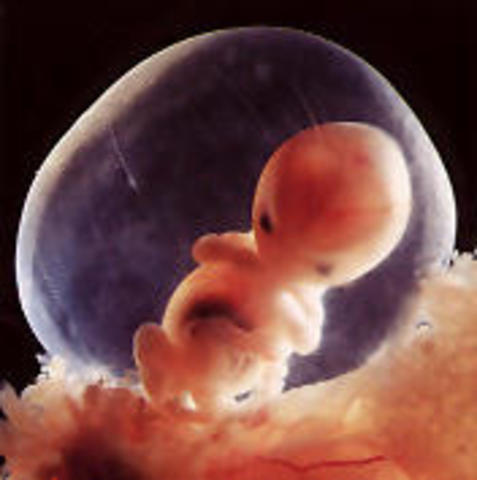

• Semana 3

Semana 3

Dentro del ciclo ovárico de la madre, ella se puede percatar de la ausencia de menstruación. A estas alturas, se comienza a formar la línea primitiva que permitirá la creación del embrión trilaminar. De igual modo, se formará la placa neural y comenzará el desarrollo de la primera glándula: tiroides. Al final de esta semana quedarán formados los primeros pares de somitas y el embrión tendrá una longitud aproximada de 1.5 mm